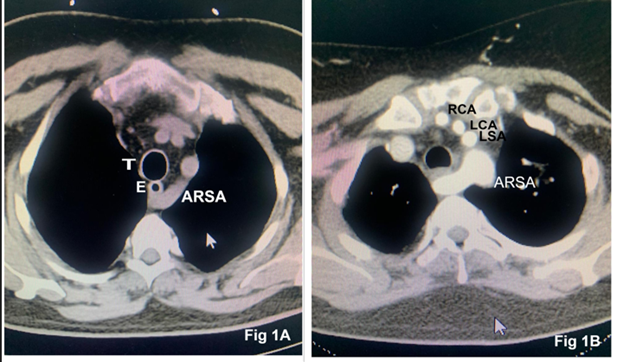

We present a case series involving two adult patients scheduled for elective cardiac surgery who were found to have ARSA. Detailed patient information is summarized in Table 1. Computed tomography (CT) of the chest confirmed the ARSA originating from the posteromedial part of the arch of the aorta distal to the origin of the left subclavian artery and coursing posterior to the esophagus in both patients (Fig 1). The retroesophageal course of the ARSA did not exhibit any compression of the esophagus or trachea. Both patients had a left-sided aortic arch along with a common origin of the right and left common carotid artery (Fig 2). The intraoperative course, including the placement of invasive monitoring lines, cannulation, and the conduct of cardiopulmonary bypass, proceeded as planned without complications. The anticipated surgical procedures and postoperative recovery were unremarkable.

Figure 1: Preoperative computed tomography showing the aberrant right subclavian artery (ARSA) coursing behind the trachea (T) and esophagus (E) (Fig 1A). Axial sections depicting the relationship of ARSA to arch vessels (RCA: right carotid artery, LCA: left carotid artery, LSA: left subclavian artery) and trachea (Fig 1